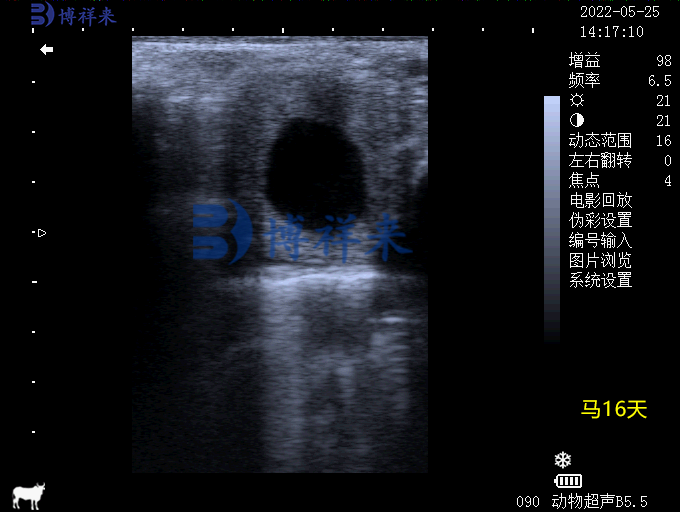

马怀孕16天妊娠B超图像

• 早期妊娠检测:在配种后11-14天,B超即可检测到受精卵是否着床,比人工触诊更早、更准确。